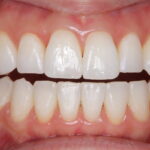

インビザライン(全体矯正)+ホワイトニングコースの症例

コンプレックスだった前歯の歪みと開咬(歯が閉じない状態)をインビザラインで美しく矯正。

・費用:935,000円(税込)

・治療期間:18ヶ月

・通院回数:18回

・32歳女性

-リスクと副作用-

・長時間マウスピースを装着するため、むし歯や歯周病のリスクがある。治療後はリテーナーを装着しないと後戻りしてしまうリスクがある。

・ホワイトニング剤の影響で知覚過敏が起こる可能性がある。色が徐々に戻る可能性がる。